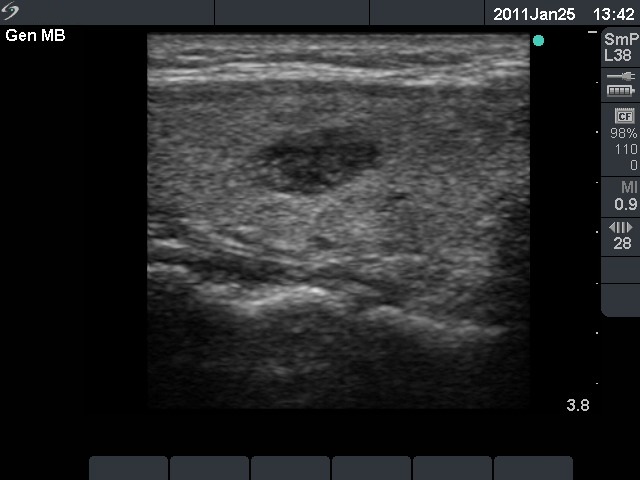

Ultrasonography: a hypoechogenic nodule with a type 3 vascular pattern in the right lobe.